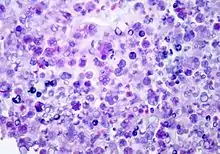

| Histologic stain of a Prototheca zopfii infection in a dog | |

Protothecosis, otherwise known as Algaemia, is a disease found in dogs, cats, cattle, and humans caused by a type of green alga known as Prototheca that lacks chlorophyll and enters the human or animal bloodstream. It and its close relative Helicosporidium are unusual in that they are actually green algae that have become parasites.[1] The two most common species are Prototheca wickerhamii and Prototheca zopfii. Both are known to cause disease in dogs, while most human cases are caused by P. wickerhami.[2] Prototheca is found worldwide in sewage and soil. Infection is rare despite high exposure, and can be related to a defective immune system.[3] In dogs, females and Collies are most commonly affected.[4]

In dogs

Disseminated protothecosis is most commonly seen in dogs. The algae enters the body through the mouth or nose and causes infection in the intestines. From there it can spread to the eye, brain, and kidneys. Symptoms can include diarrhea, weight loss, weakness, inflammation of the eye (uveitis), retinal detachment, ataxia, and seizures.[11]

Dogs with acute blindness and diarrhea that develop exudative retinal detachment should be assessed for protothecosis.[6] Diagnosis is through culture or finding the organism in a biopsy, cerebrospinal fluid, vitreous humour, or urine. Treatment of the disseminated form in dogs is very difficult, although use of antifungal medication has been successful in a few cases.[4] Prognosis for cutaneous protothecosis is guarded and depends on the surgical options. Prognosis for the disseminated form is grave. This may be due to delayed recognition and treatment.[3]